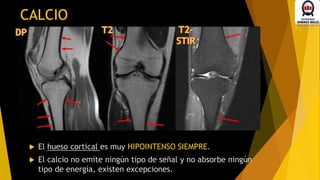

CALCIO

 El hueso cortical es muy HIPOINTENSO SIEMPRE.

 El calcio no emite ningún tipo de señal y no absorbe ningún

tipo de energía, existen excepciones.